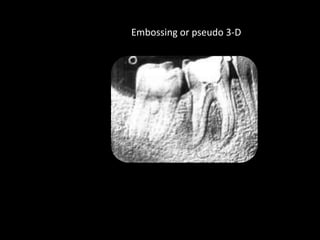

4. Digital radiography provides advantages like automated measurements and image manipulation but has higher initial costs and bulkier sensors.